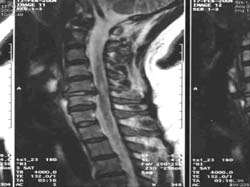

<Á¤»ó

°ñ ±¸Á¶> <°ñ´Ù°øÁõÀÇ

°ñ ±¸Á¶>